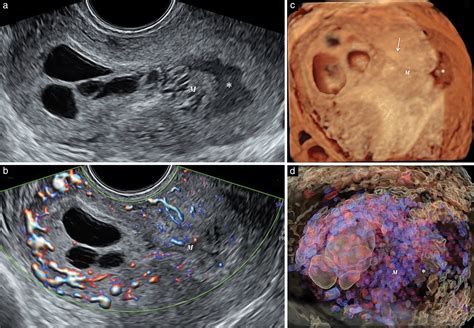

Ultrasound imaging reveals several distinctive features that are indicative of a molar pregnancy. These features include:

• Snowstorm Appearance: This is a classic ultrasound finding in complete molar pregnancies, where the uterus appears filled with small, grapelike cysts.

• Theca Lutein Cysts: These are ovarian cysts that can develop in response to high hCG levels and are often seen in molar pregnancies.

• Absence of Fetal Pole: In complete molar pregnancies, there is no visible fetal pole or yolk sac.

• Partial Molar Pregnancy Features: In partial molar pregnancies, there may be a visible fetal pole, but it is often abnormal, and the placenta shows cystic changes.

These ultrasound features are crucial for differentiating molar pregnancies from other gestational abnormalities.